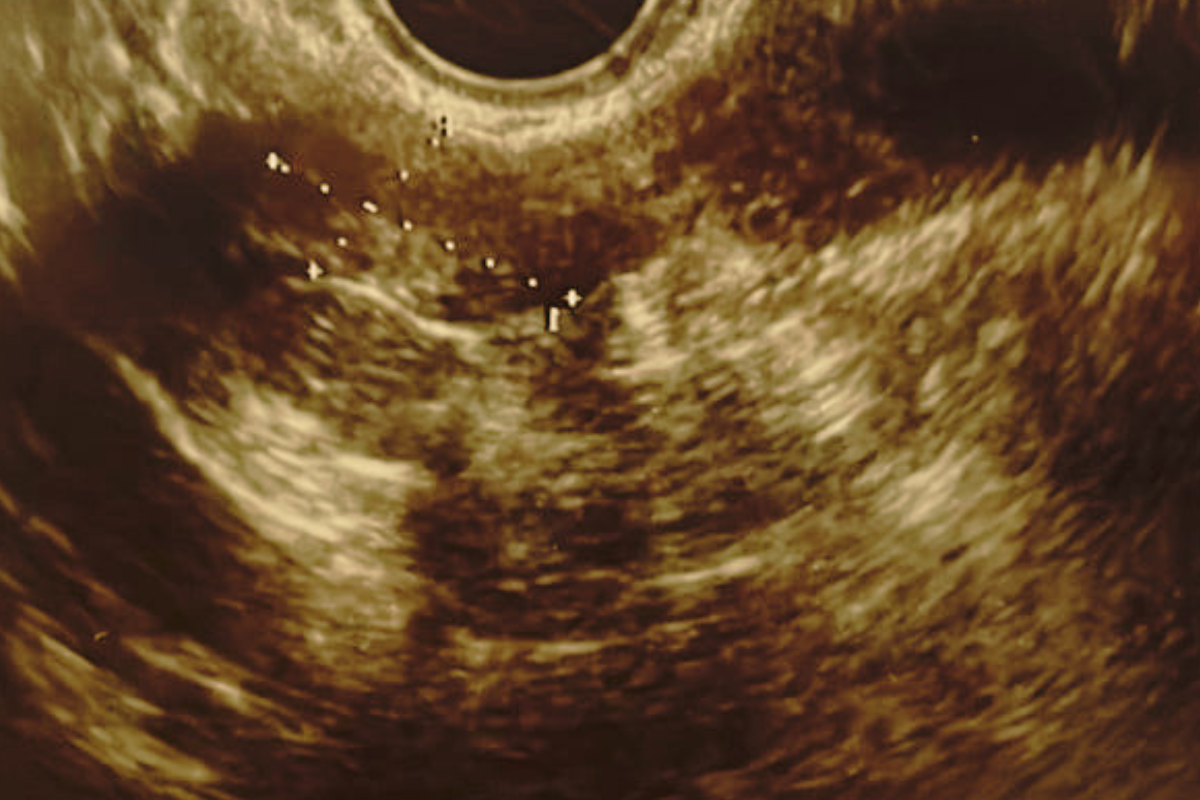

Показания врачей в другой клинике: предложено хирургическое лечение в объеме надвлагалищной ампутации матки без придатков (выявлен крупный интерстициально-субмукозный миоматозный узел 6х4.7х 5.2 см.)

Далее пациентка прошла курс лечения телесной терапии и лекарственными препаратами у нашего остеопата и гинеколога. Пациентке трижды производилось ультразвуковое исследование малого таза: через три месяца после прохождения программы и через 6 месяцев

Результаты лечения Вы можете видеть на фото.

В начале 2024 года начались задержки менструального цикла, до 2-х недель, обильные и болезненные выделения. На УЗИ размер нескольких миоматозных узлов уже 48х 37 мм, 28 х 35 мм, 43 х36 мм. Так как наблюдался рост новообразований были показания к операции и в другой клинике меня направили на операцию. Я не хотела делать операцию и принимать гормональную терапию и обратилась в Центр лечения миомы без операции при клинике Нео Вита по рекомендации.

На сегодняшний день нормализовался цикл, ушла боль, улучшилось настроение и общее состояние. Значительно изменились процессы в личной жизни- это тоже хочу отметить. Размеры узлов 23 х14,12 х15 мм. Это большой прогресс, ведь я понимаю, когда убрать у болезни причину – она не вернется и терапия медикаментозная на нужных этапах лечения действительно быстро помогает.